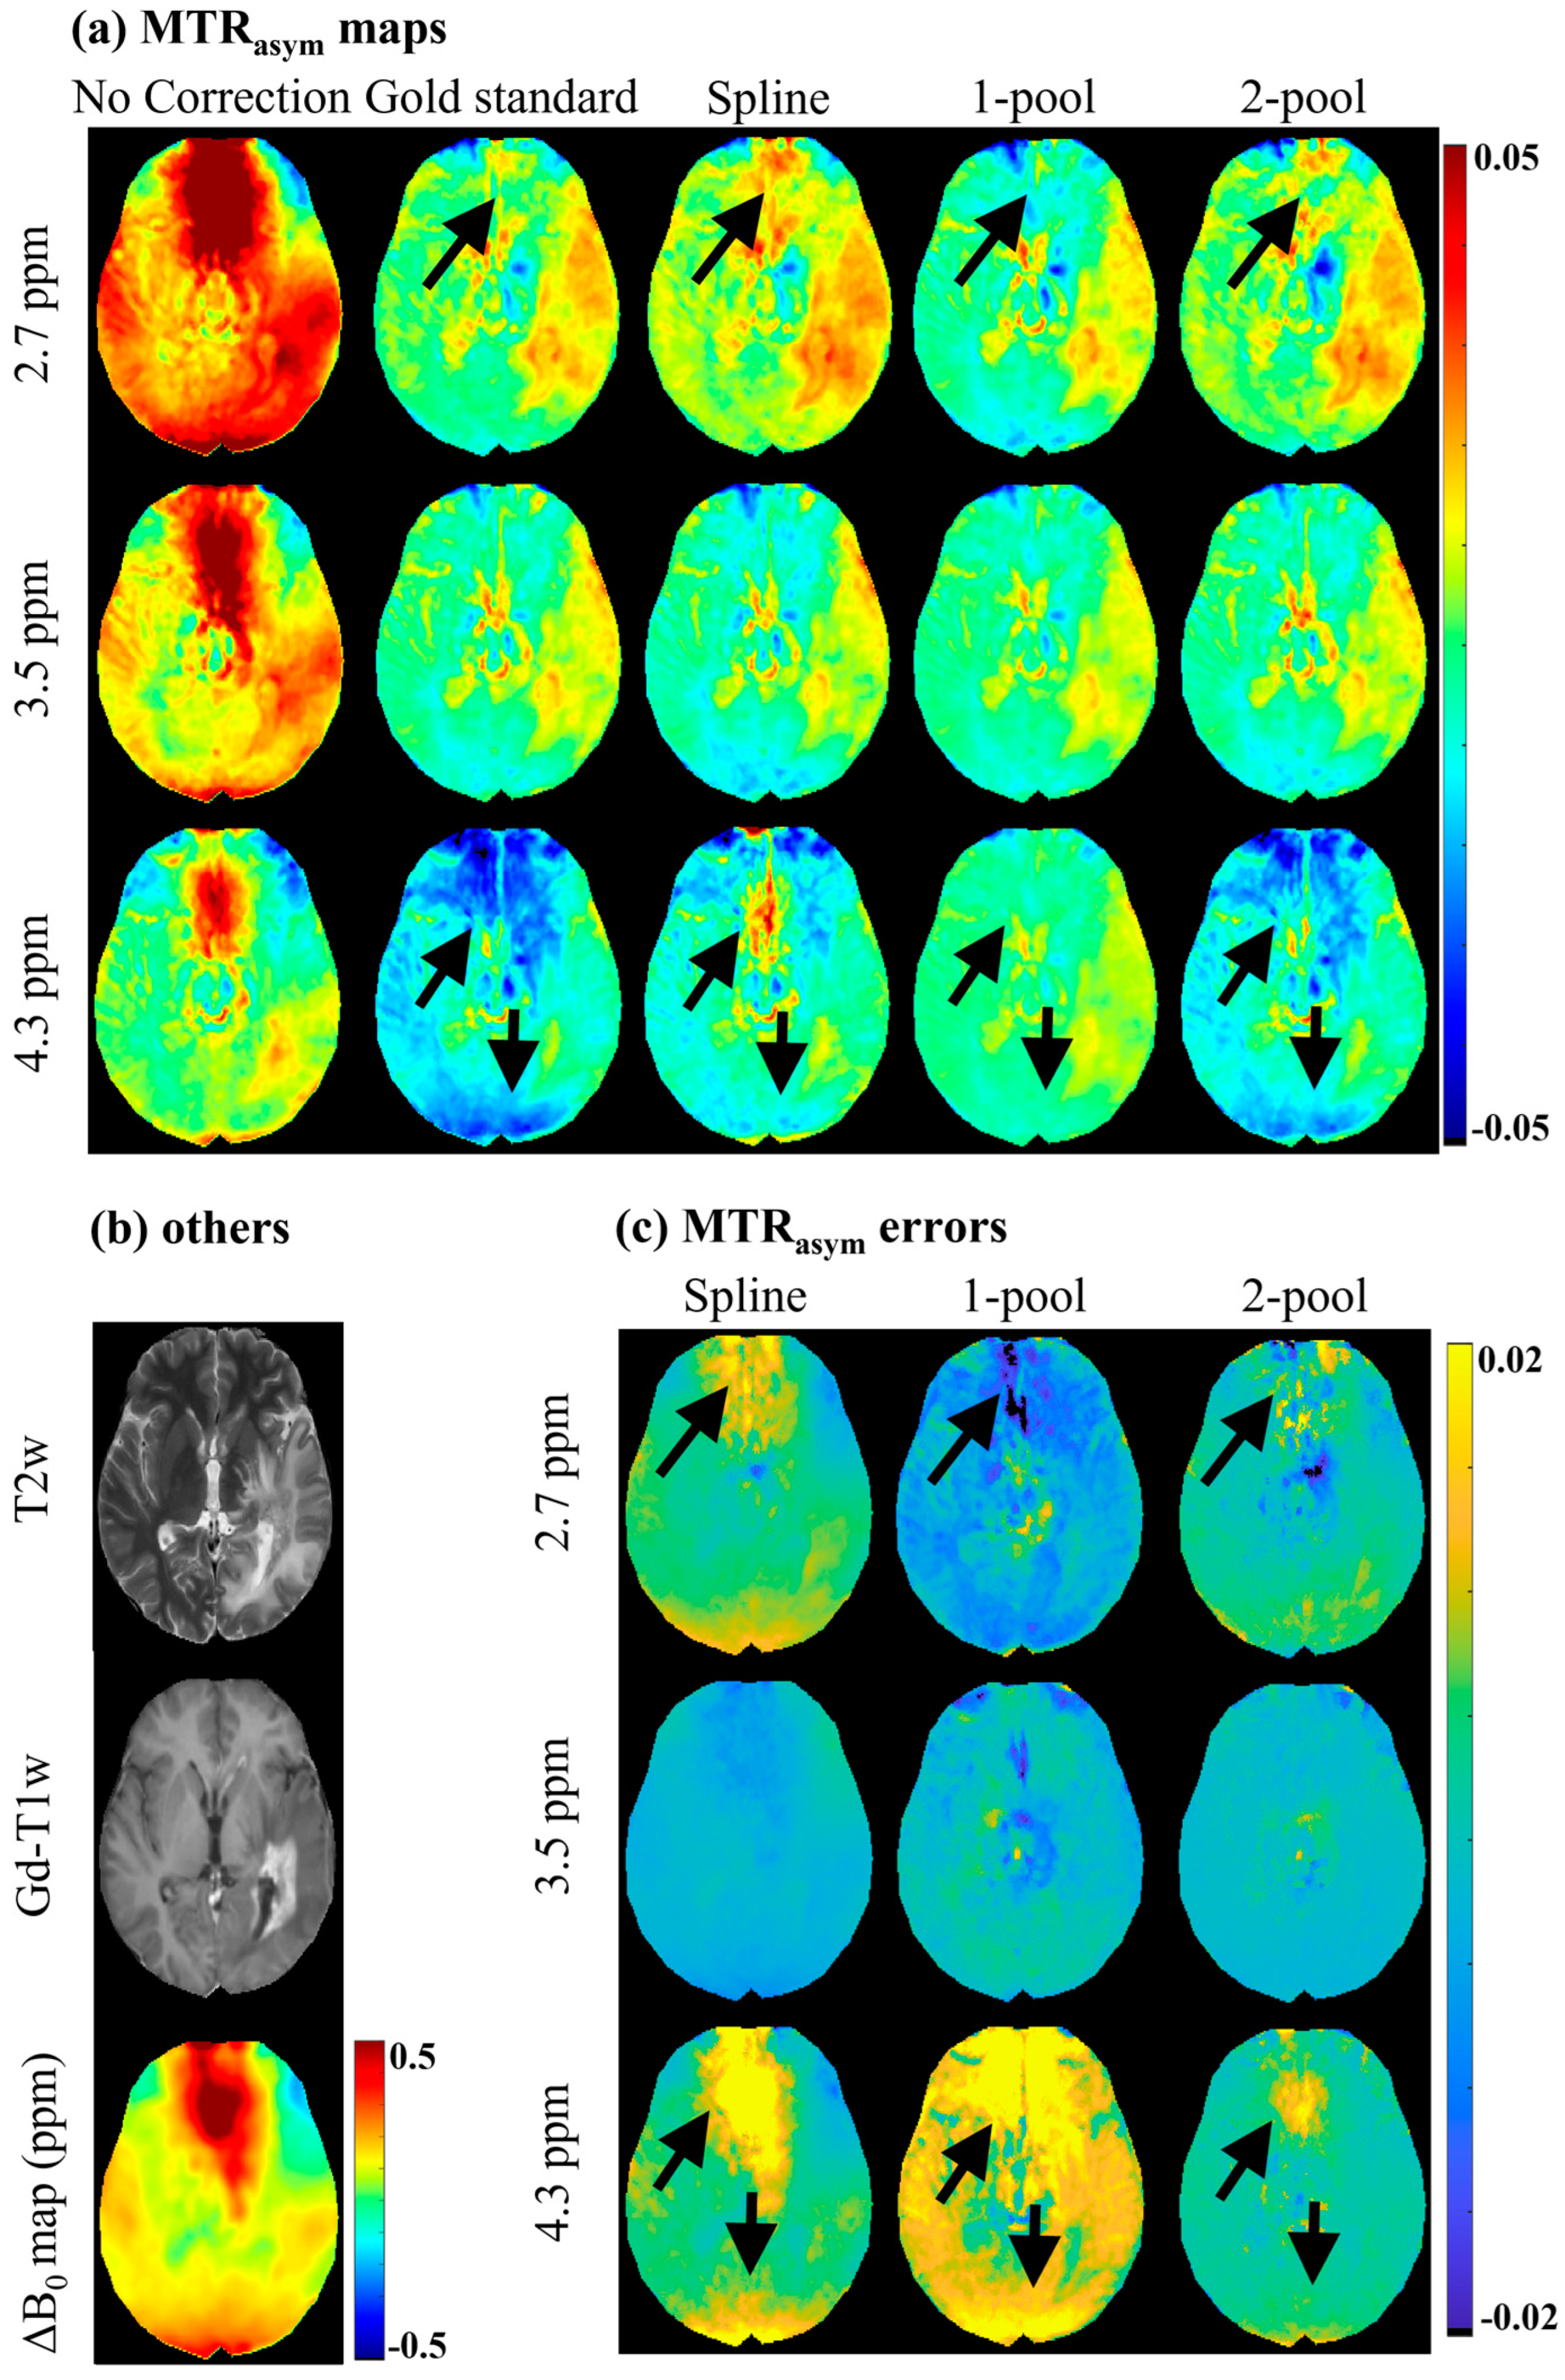

4. Results

4.1. Accuracy Evaluation